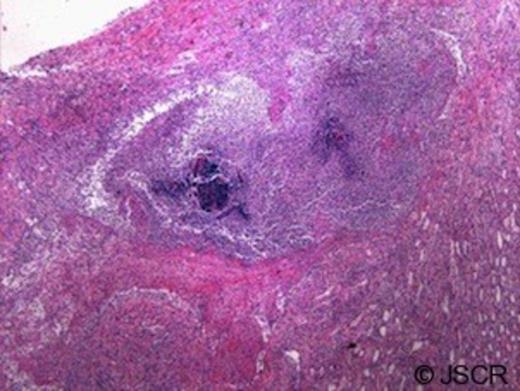

Pathologic examination of the removed kidney demonstrated active infection with bacteria and microabscess (Figure 3). In addition, the granulomatous and necrotising inflammation seemed to coalesce in a fistulous tract toward the renal capsular surface with a surrounding haematoma (Figure 4). Delayed review of the slides following the discovery of his HIV status demonstrated classic focal segmental glomerulosclerosis.

Renal medulla with bacteria, microabscess, and neutrophil reaction (10x magnification)